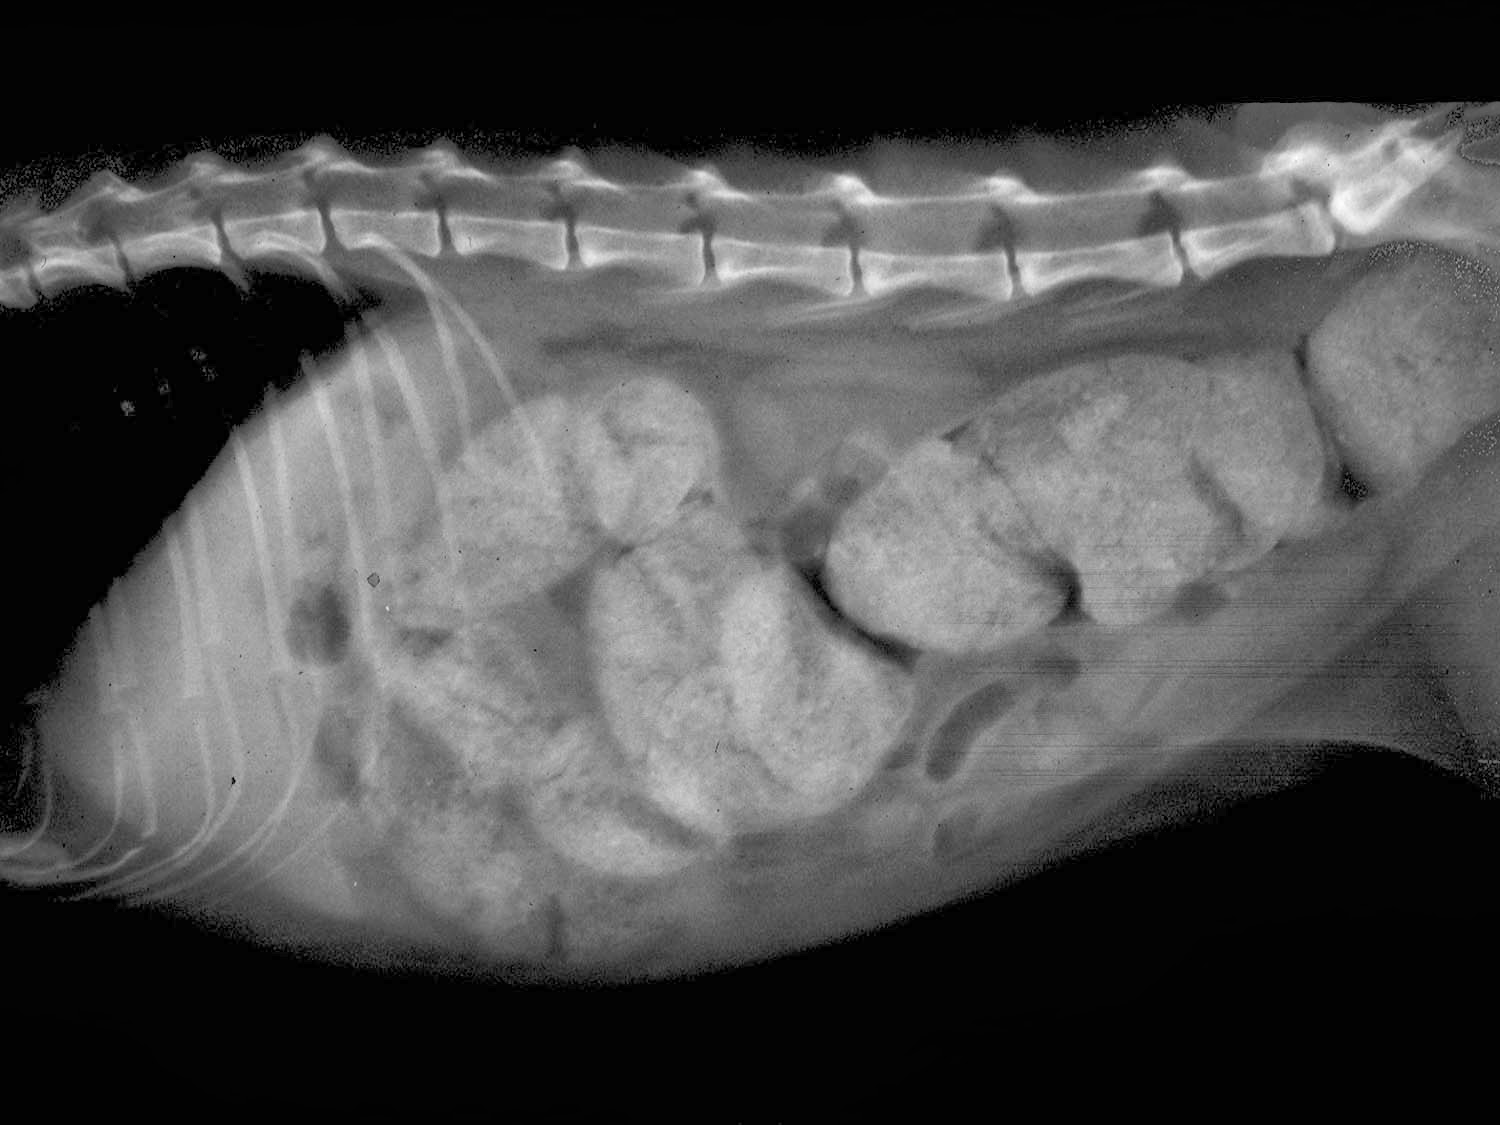

- Рентген брюшной полости (для исключения мегаколона, калового завала, опухолей, инородных предметов в кишечнике),